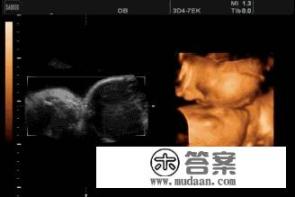

孕80天的时候,双胞胎胎儿在肚子里的样子是怎么样的?双胞胎胎儿在孕期80天时肚子的具体样子是怎样的呢?

孕80天双胞胎胎儿在肚子里的样子大致为:身体长度约为3\~4厘米,已经能够分辨出头部和身体,但大部分仍在母体的羊膜囊内,胎儿处于快速发育阶段,四肢开始活动,心脏等重要器官开始工作,由于双胞胎的存在,母体的腹部隆起可能更加明显,但具体表现还取决于胎儿的体位和母体的身体状况,胎儿发育尚未完全,仍需密切关注和照顾。

孕80天,双胞胎胎儿在妈妈肚子里的状态是怎样的呢?

到了孕80天,双胞胎宝宝就像两个小小的鸡蛋一样,大小开始逐渐发育,定期去医院做产检是非常重要的,这样可以帮助我们了解宝宝们发育的情况,由于怀着两个孩子,妈妈会更容易感到疲劳,所以平时不要长时间走动,可以在家人的陪同下适当散步,这对未来的生产也会有所帮助。